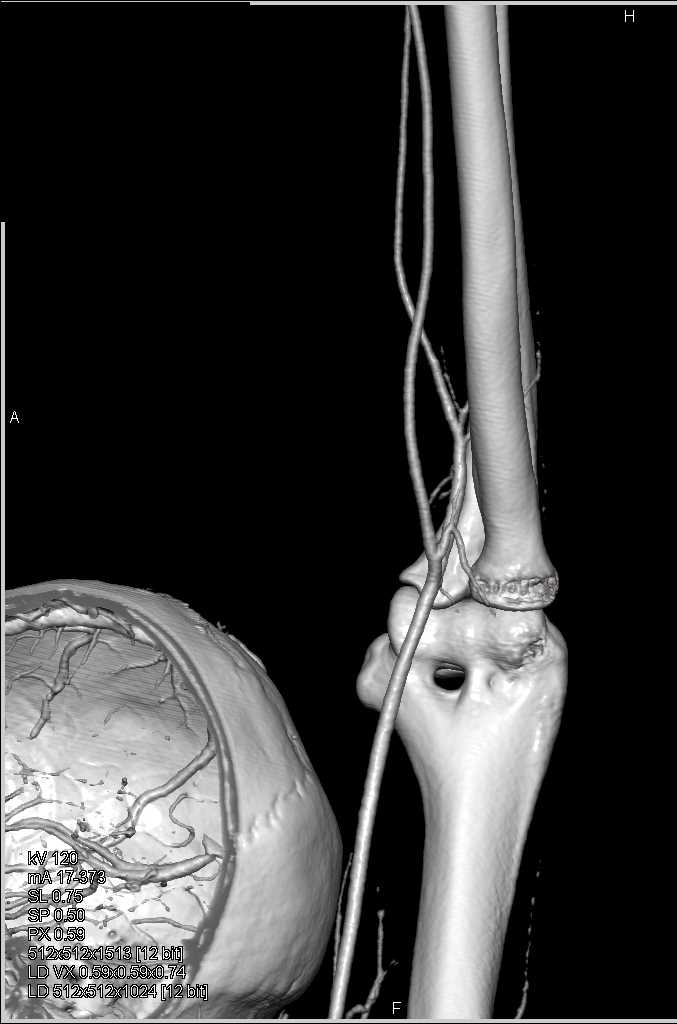

Soft Tissue Injury with Patent Vessels